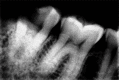

Successful endodontic treatment relies upon a thorough knowledge of root canal anatomical variations along with proper diagnosis, treatment planning, and clinical expertise. One of the difficult root canal configurations that are frequently encountered commonly in mandibular second molars is C-shaped root canal. Due to the intricate root canal configuration, it is often difficult to negotiate, debride, and obturate such canals leading to failure of root canal treatment. Understanding the anatomical variation and adequate visualization will enable the clinician to manage these cases effectively. Advanced irrigation and obturation techniques help in managing such anomalous canal configurations. This article presents the management of two different C-shaped root canal configurations under dental operating microscope using thermoplasticized obturation techniques.